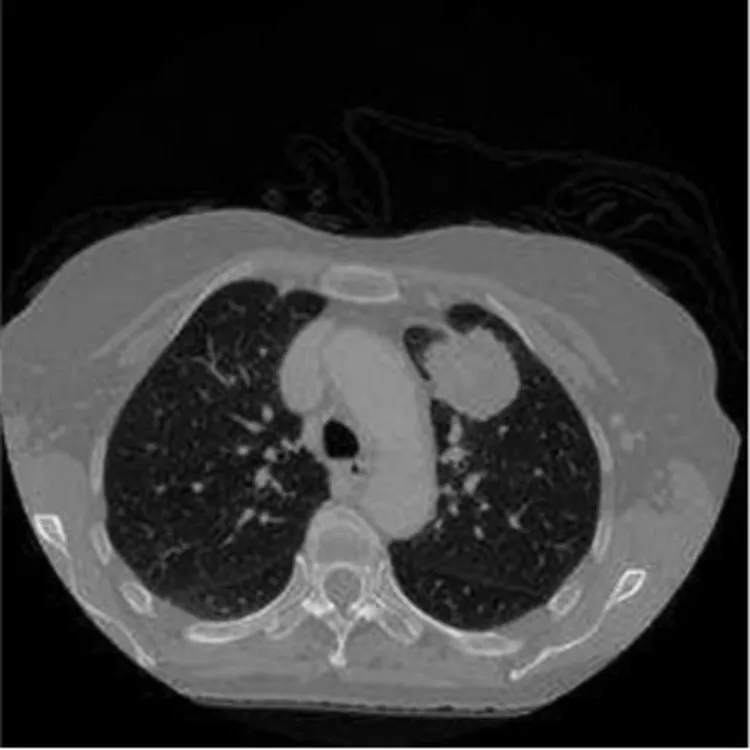

موضوع اصلی این مقاله یک توسعه از الگوریتم مبتنی بر پردازش تصویر پزشکی برای جداسازی تومور ریه در تصاویر CT است که به دلیل عدم وجود چنین الگوریتمی ها و رویکردهای مورد استفاده برای تشخیص تومور است.